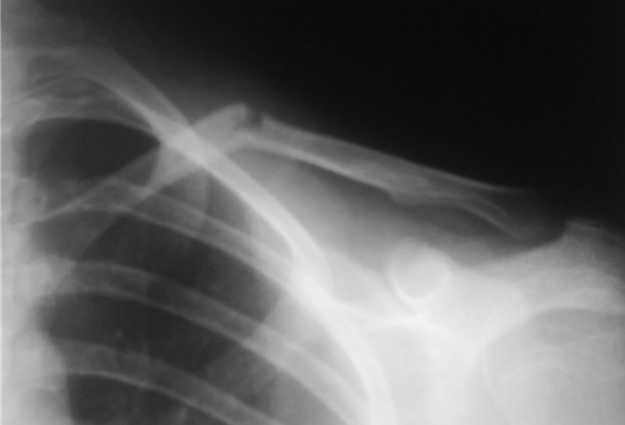

Девочка 14 лет, на даче упала с турника 05-07-08, в наш травмпункт обратились на следующий день - Диагноз: Закрытый перлом диафиза левой ключицы. Дежурным травматологом наложена 8-образная гипсовая повязка. На следующий день, родители привели девочку с жалобами на давление в левом надплечье и онемение правого предплечья и 1,2, 3-го пальцев кисти.

Мной была немедленно снята наложенная накануне повязка, и заменена на марлевую Дезо. 09-07-го, Дезо заменена на "косыночную" повязку.Сегодня произведен контрольный снимок -На сегодняшний день сохраняется онемение 1-3 пальцев.